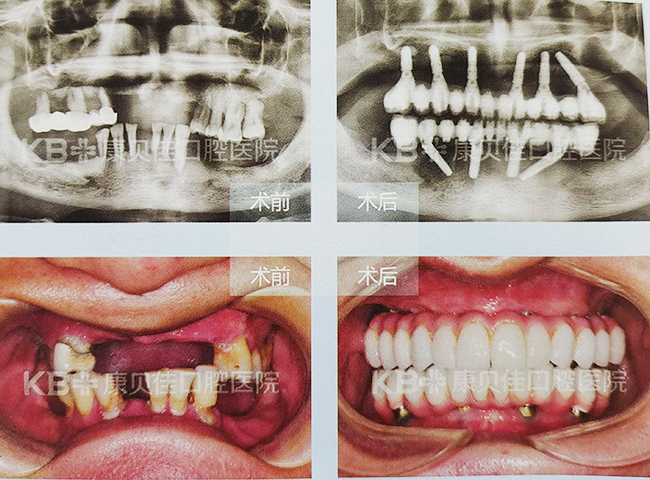

钱先生 43岁

因为喜欢吸烟又不太注重口腔卫生,30多岁时就饱受牙龈炎困扰,导致牙齿逐渐松动、脱落,剩余的牙齿也无法保留。到康贝佳拔掉患牙后采用即刻恢复技术重建满口好牙,全程微创、无痛,用起来就像真牙一样。

治疗方案:

上颌种植6颗恢复半口 下颌种植8颗恢复半口